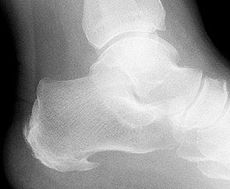

Τα ακτινολογικά ευρήματα δεν είναι καθόλου ενδεικτικά, γι” αυτό η διάγνωση θα στηριχθεί κυρίως στην κλινική εικόνα. Η αύξηση της πυκνότητας και ο κατακερματιομός του πυρήνα της οπίσθιας απόφυσης της πτέρνας μπορεί να αποτελεί φυσιολογικό εύρημα και μόνο σε σύγκριση προς την άλλη πτέρνα πρέπει να αξιολογείται.